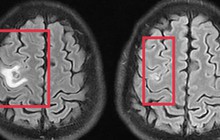

Eczema hay còn gọi là bệnh chàm, là một bệnh ngoài da phổ biến có thể xuất hiện ở bất cứ ai, bất cứ độ tuổi nào. Bệnh gây ra các đợt viêm nhiễm trên da với các triệu chứng điển hình là da bị đỏ, nổi mụn nước kèm theo ngứa ngáy khó chịu. Việc bạn nạp quá nhiều thực phẩm giàu protein vào cơ thể như trứng, cá, thịt bò... làm tăng nguy cơ gây dị ứng cao. Thay vào đó, khi bị eczema bạn nên ăn các thực phẩm chứa Omega 3 như quả óc chó, đậu nành, cá hồi... giúp ngăn ngừa nếp nhăn và tránh da bị viêm nhiễm, nổi mụn trứng cá.